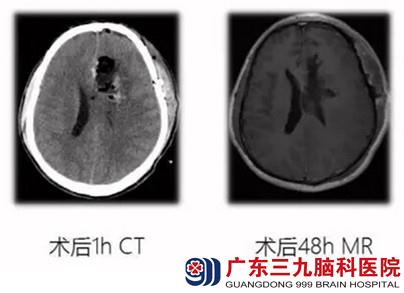

入院第三天,在全麻下行左额叶肿瘤切除术,病理:胶质母细胞瘤WHO IV级。术后精神好转,意识清楚,查体:KPS80分,手术切口愈合良好,右侧肢体肌力V级弱。